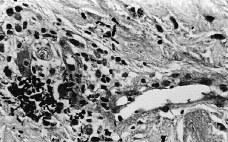

Se realizó biopsia cutánea para estudio histopatológico y cultivo. En 48 horas se recibieron los cultivos en sangre y piel con crecimiento de Trichosporon asahii, por lo que se añadió fluconazol al tratamiento. La paciente quedo afebril, pero se mantuvo la pancitopenia, con disnea y anuria, falleciendo 5 días después. El estudio histológico confirmó el tromboembolismo micótico que ocupaba la luz y pared vascular, que con la tinción de PAS ponía de manifiesto numerosas hifas y conidias (Figs. 3 y 4).

FIG. 3.--Presencia de abundantes hifas y esporas en zonas perivasculares de dermis media.

FIG. 4.--Hifas en luz vascular y zona extravascular. (PAS, ×400.)